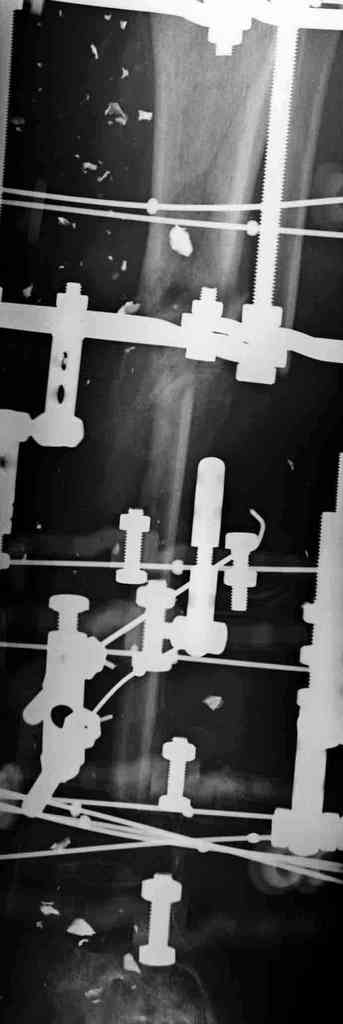

5. Ну и чтобы не быть голословным. Молодой человек подорвался на фугасе (Чечня, 2005 год). Свежие рентгенограммы:

Соответственно ожоги и дефект мягких тканей, переломы костей стопы и пр. Наложили аппарат

Илизарова (как придется), хирургически обработали и героически заживляли мягкие ткани с многочисленными кожными пластиками. В итоге через полгода я принял его вот таким:

Реализовал описанную выше методику, и в итоге вот что получилось. Высылаю лишь прямые проекции,

в боковых тоже всё в тему.

Очень пригодились карбоновые кольца (Джолдас -огромное спасибо, я твой должник!!!), поскольку остеопороз дистального отломка был просто невероятный. На цифровом рентгене с трудом угадывались контуры.

Рентген в процессе перемещения - внизу карбоновые кольца, тракция фрагмента спицами с упором.

внешний вид в аппарате - не завершающем этапе, сначала стопа тоже была фиксирована в аппарате.

Сейчас аппарат сняли, но случай ещё не завершенный.

Признаюсь честно, не совсем уверен в прочности консолидации на стыке косточек. Кроме того, укорочение в районе 6 см. Сейчас реабилитация - ходит опираясь на ногу с одним костылем.

Продолжение, видимо, будет... Возможно, будем удлинять.